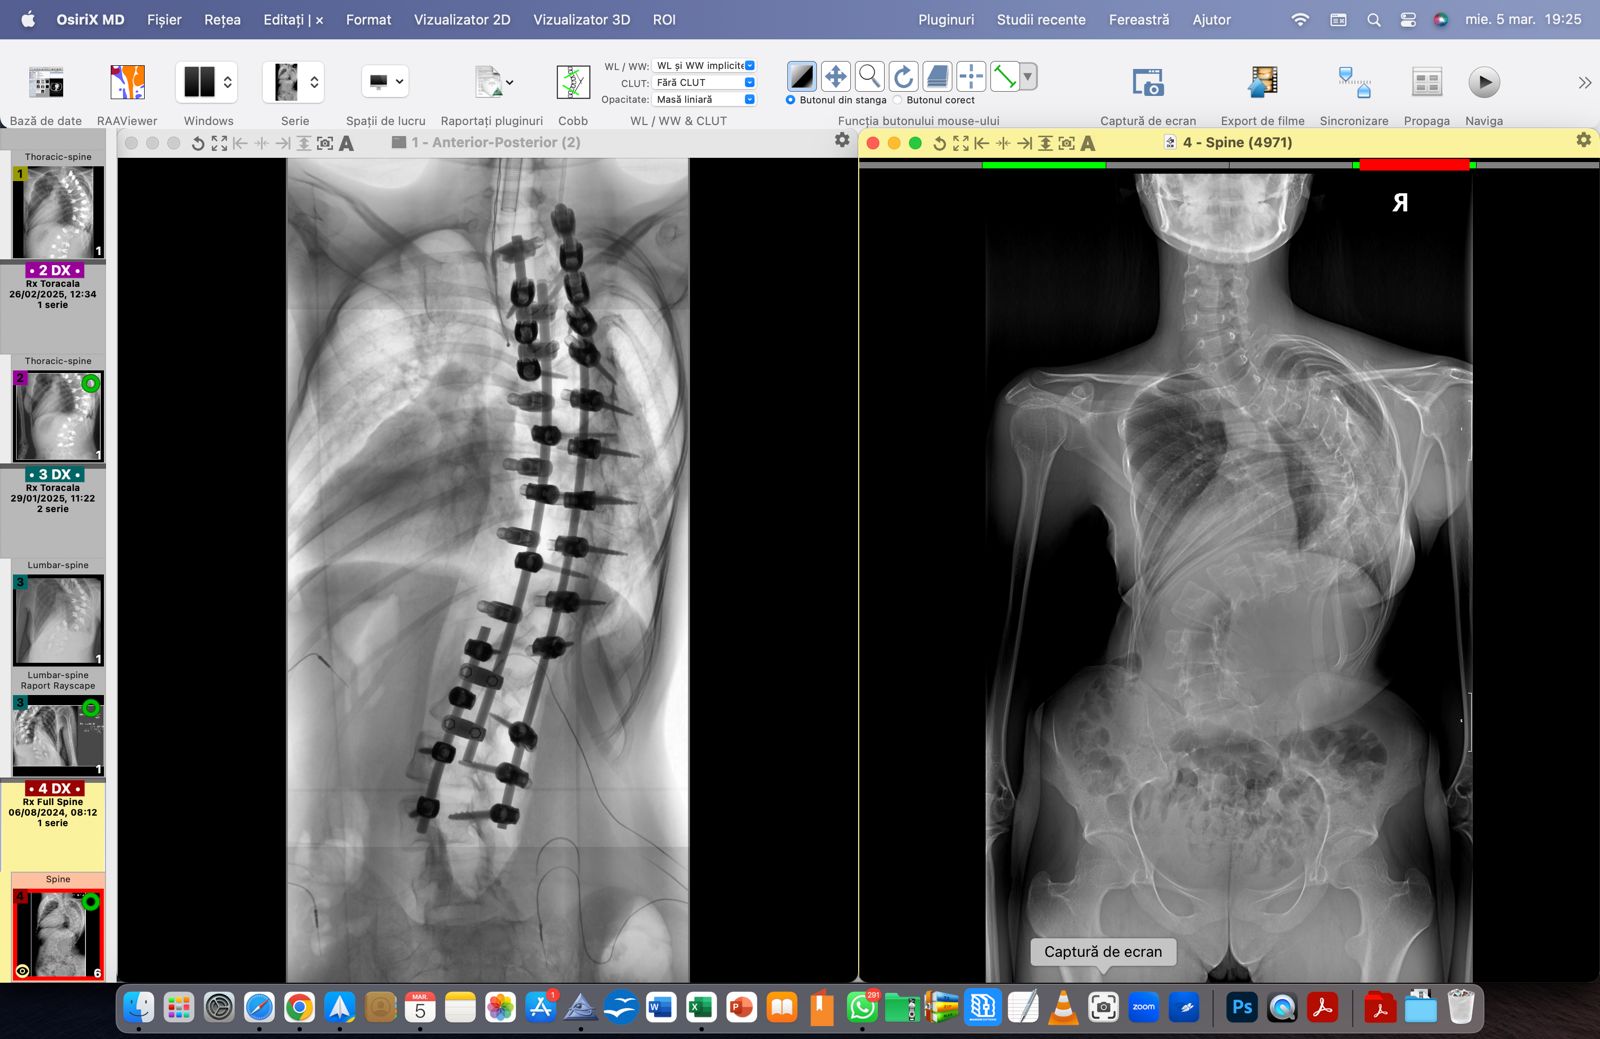

Denisa – o luptătoare de doar 15 ani – se întoarce acasă! Cu inima plină de recunoștință și cu speranță în suflet. După două intervenții dificile, un unghi Cobb de 143° a devenit 57°! O diferență uriașă care înseamnă nu doar o coloană mai dreaptă, ci o viață nouă, o șansă reală la normalitate.